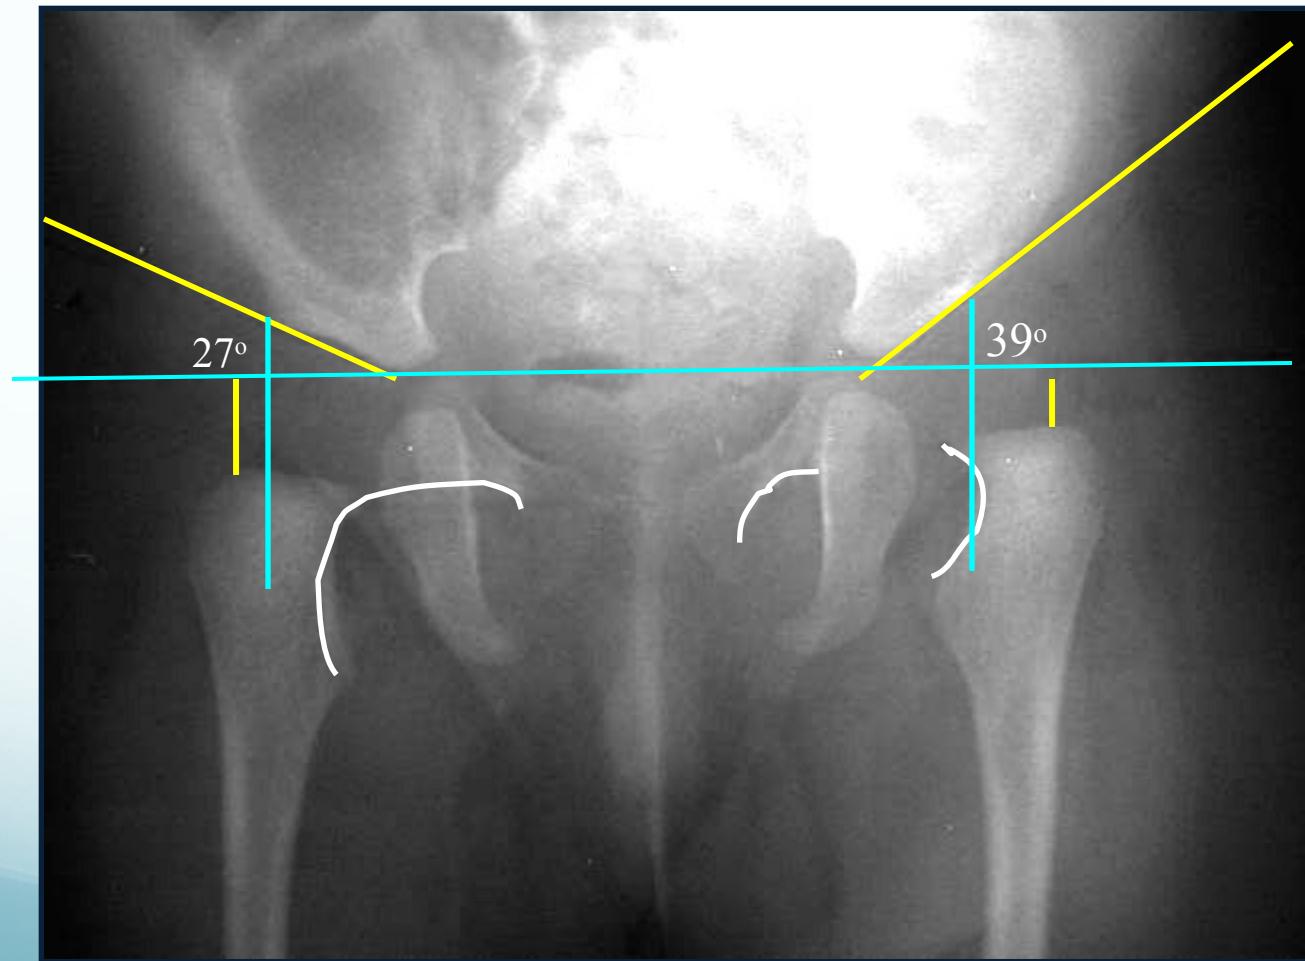

Radiographic Measurements

Perpendicular line from edge of acetabulum:

- Dislocated: Lateral to perpendicular line

- Normal: Medial to perpendicular line

Acetabular angle (acetabular index):

- Normal: ≤ 25°

- Dislocated: > 35°

Shenton’s line: